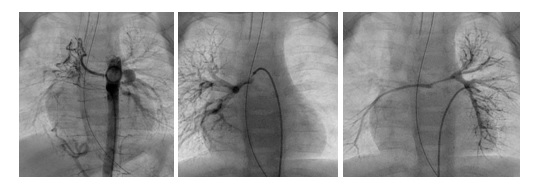

Badania angiograficzne tego samego pacjenta. Wskaż odpowiedni do obrazów opis: